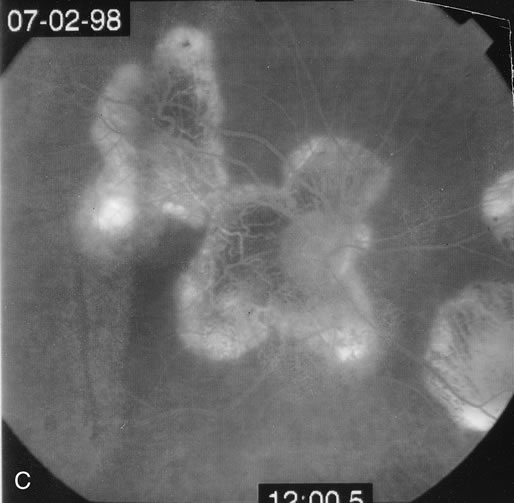

Classically, there are broad areas of chorioretinal atrophy that may take a jigsaw pattern. Usually the atrophy is centered on the disc and spreads along the vascular arcades and then towards the fovea. Sometimes the choroiditis starts within the macula and spreads out from there. Both eyes tend to be affected although there may be marked asymmetry between the two eyes. The active disease appears as yellow-gray areas. If there is evidence of previous disease, then the active areas tend to be at the edge of the chorioretinal atrophy (Figs. 16 to 18). Rarely, there may be several noncontiguous areas of chorioretinal atrophy in the eyes. Retinal vasculitis at the site of an active lesion and retinal vein occlusions may rarely be seen.

Fig. 16. A. Color fundus photograph showing the jigsaw pattern of choroidal and retinal atrophy extending from the disc along the arcades. At the inferior edge of the superotemporal lesion there is a recurrence noted by the grayness of the retina. B. Fluorescein angiogram in the laminar venous phase showing a large window defect in the area of inactive choroiditis and blockage of the choroidal fluorescence in the area of active choroiditis. C. In the late phase of the fluorescein angiogram there is staining of the edges of the inactive choroiditis and marked hyperfluorescence in the area of active choroiditis.

Fig. 17. A. Classic inactive case of serpiginous choroiditis showing the jigsaw pattern of disease surrounding the fovea. B. Fluorescein angiogram showing staining of the edges of the inactive serpiginous choroiditis. There is blocked fluorescence in the areas of hyperplasia of the retinal pigment epithelium. C. Indocyanine green angiogram showing absence of fluorescence in the area of inactive choroiditis.